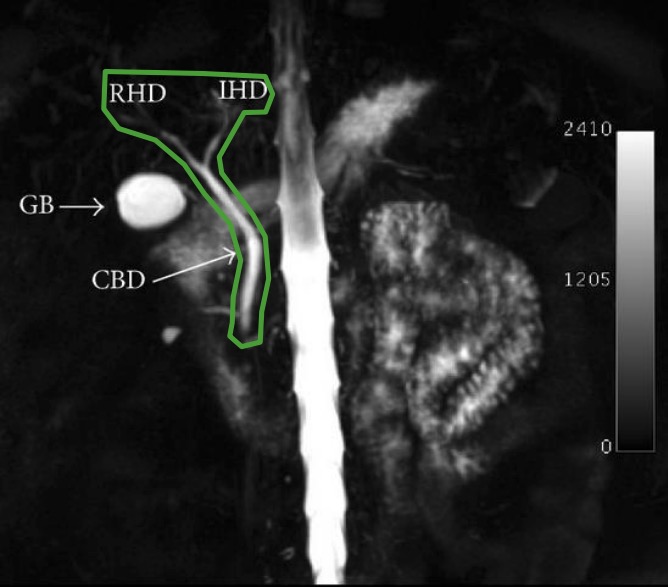

MRI MRCP Anatomy Free MRI Coronal Cross Sectional Anatomy of the

From mrimaster.com